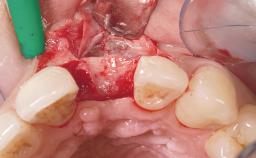

A 30-year-old female patient was referred to the office for the treatment of tooth 11. Her chief concern at the initial visit was to inquire, “Why is my tooth pink?” Upon clinical examination, it was determined that tooth 11 had a previous history of trauma and that the clinical crown had become noticeably pink in color as a result of internal resorption. This diagnosis was confirmed radiographically, indicating a large radiolucency involving the central and distal portions of the clinical crown. It was determined that restoration of this tooth was not possible, and that extraction was indicated. The presence of a mid-line diastema, which the patient wanted to reproduce, directed the treatment plan for tooth replacement utilizing a dental implant.

Bone Augmentation Horizontal|Simultaneous

Augmentation Materials Autogenous chips|Membrane

Socket Integrity Sufficient, with intact bone walls

Bone Volume Sufficient, with intact walls